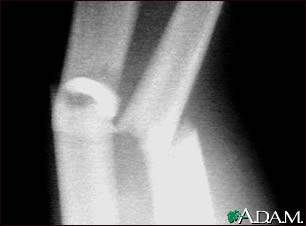

Fracture, forearm - X-ray

This x-ray shows broken (fractured) forearm bones (radius and ulna).